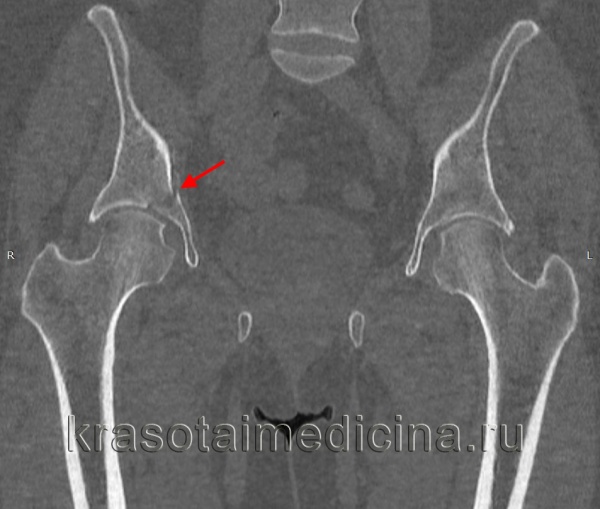

Для определения костного фрагмента обычно достаточно снимка в переднезадней проекции. Неоссифицированные апофизы иногда могут затруднить интерпретацию рентгенограмм, поэтому читателю для внесения ясности в этот вопрос рекомендуем обратиться к началу этой главы.

Рентгенография таза помогает уточнить диагноз, однако в ряде случаев снимков не достаточно для достоверного подтверждения перелома таза, поскольку линию перелома бывает трудно отличить от зоны роста. При возникновении затруднений пациента направляют на МРТ или КТ костей таза. Консультации других специалистов, как правило, не нужны.

Для уточнения диагноза выполняют обзорную рентгенографию таза и рентгенографию поврежденного сустава в трех дополнительных проекциях. По возможности пациента направляют на КТ таза, поскольку эта методика позволяет более точно оценить тяжесть травмы и характер смещения отломков. Диагностическая ценность компьютерной томографии возрастает при повреждениях задней колонны и оскольчатых переломах.